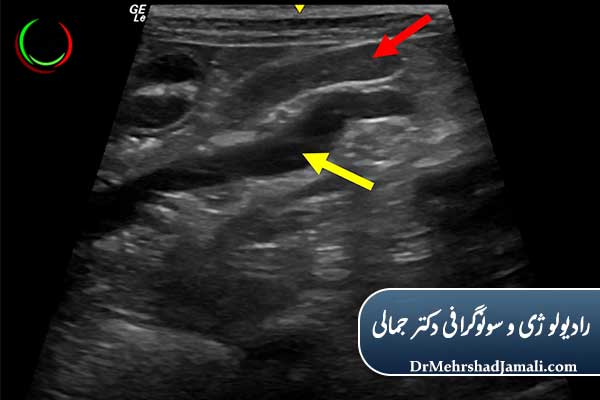

تفاوت غدد لنفاوی طبیعی و غیرطبیعی در سونوگرافی

در سونوگرافی، پزشک ویژگیهای زیر را بررسی میکند:

| ویژگی | غده طبیعی | غده غیرطبیعی |

|---|---|---|

| شکل | بیضی و کشیده | گرد و نامنظم |

| مرکز غده (hilum) | روشن و مشخص | از بین رفته یا تیره |

| اندازه | معمولاً کمتر از ۱ سانتیمتر | بیش از ۱ سانتیمتر یا در حال رشد |

| الگوی عروقی | طبیعی و منظم | افزایش جریان خون غیرطبیعی |

| مرز غده | صاف و یکنواخت | ناهموار یا تهاجمی |

وجود این تغییرات میتواند نشانه عفونت یا حتی بدخیمی باشد که در این صورت ممکن است پزشک درخواست سونوگرافی رنگی (داپلر) یا نمونهبرداری (FNA) دهد.